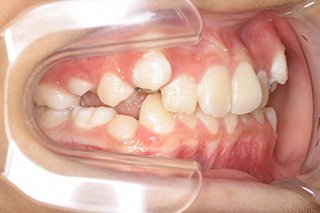

顎顔面矯正症例 11歳女児 Case

| 主訴 | 永久歯が変な所からはえてきている|顔貌 | |

|---|---|---|

| 施術内容 | 矯正1期治療 | |

| 治癒期間 | 1年5ヶ月間 | |

| 費用 | 459,200円(税込) | |

| リスク・ 副作用 | 痛みを伴う | |